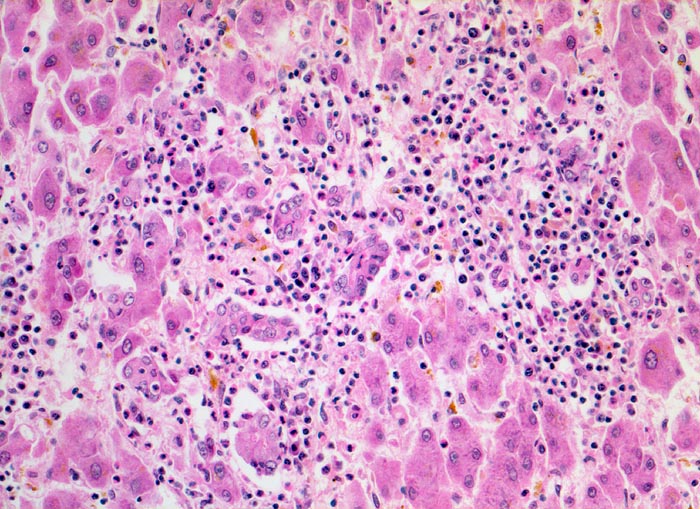

PathoPic ID 5137 - akute Hepatitis

akute Hepatitis

Entzündung infektiös

Leber

Portalfeld mit gemischtem Entzündungsinfiltrat.

siderinbeladene und zeroidbeladene Makrophagen.

Autopsiepräparat eines 37jährigen Patienten mit Transaminasenanstieg und Hyperbilirubinämie. St.n. Bluttransfusionen

Histologie

200